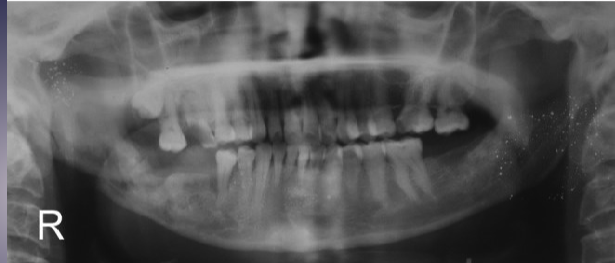

2 radiographic signs of pericoronitis

periosteal reaction

sclerotic bone reaction (radiopaque)

what are the white + black arrows

white: periosteal rxn

black: sclerotic bone rxn

of pericoronitis